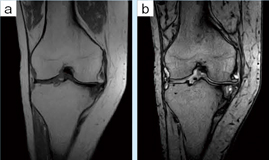

■症例2:関節リウマチ,変形性膝関節症

73歳,女性。基礎疾患としてリウマチがあり,両膝の変形性関節症(OA)も進行している。MRI検査は,単純X線ではわかりにくい軟骨の磨滅の程度,骨壊死の範囲などを確認でき,手術適応の判断には重要な検査である。 a:T1WI,COR,FOV:200mm,TR/TE:460/16,FA:90°,スライス厚:3mm b:T2*WI,COR,FOV:200mm,TR/TE:790/15,FA:30°,スライス厚:3mm